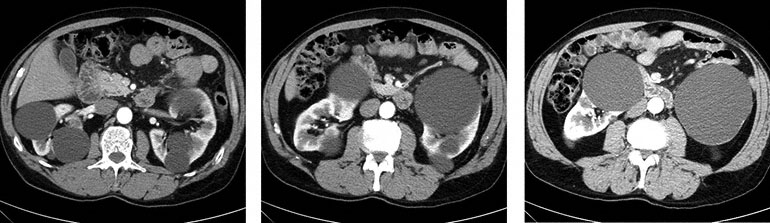

A 55-year-old man comes to the emergency department 1 hour after the sudden onset of severe left abdominal and flank pain; he also has had blood in his urine during this period. He has not had fever, chills, or difficulty with urination. His family history is unknown because he was adopted. He appears to be in pain. Temperature is 37.2°C (99.0°F), pulse is 110/min, and blood pressure is 140/100 mm Hg. Pulmonary and cardiac examinations disclose no abnormalities. Abdominal examination discloses a palpable, tender mass in the left upper quadrant and a mass in the right upper quadrant. Serum studies show a creatinine concentration of 2.4 mg/dL. CT scans of the abdomen are shown. This patient is at greatest risk for which of the following?